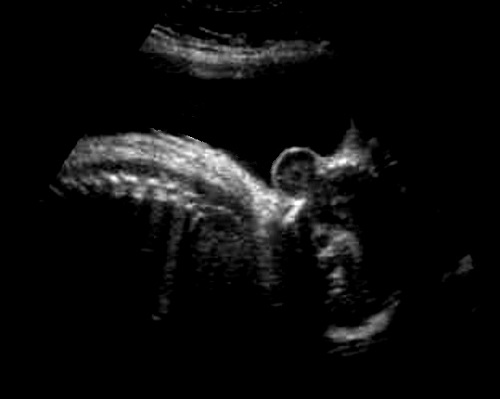

E' caratterizzata da anomalie dell'apparato muscolo-scheletrico (quadro di distrofia muscolare congenita con contratture articolari, scoliosi), anomalie cerebrali (lissencefalia tipo II, ipoplasia cerebellare, idrocefalia, encefalocele, malformazione di Dandy-Walker), anomalie oculari (distacco di retina, cataratta, microftalmia).

La diagnosi ecografica prenatale, non sempre possibile e spesso tardiva, si basa su:idrocefalia, lissencefalia, ipoplasia cerebellare,encefalocele, scoliosi, microftalmia, disgenesia del corpo calloso (lipoma del corpo calloso).

Meno frequentemente possono presentarsi la malformazione di Dandy-Walker, microcefalia, agenesia del corpo calloso.